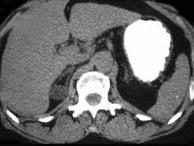

问题 女,35岁,无意中发现血压高,实验室检查:血和尿中醛固酮水平增高,请结合所提供图像,作出诊断()

选项 A.右肾上腺增生 B.右肾上腺Cushing腺瘤 C.右肾上腺皮质腺瘤 D.右肾上腺转移瘤 E.右肾上腺囊肿

答案 C